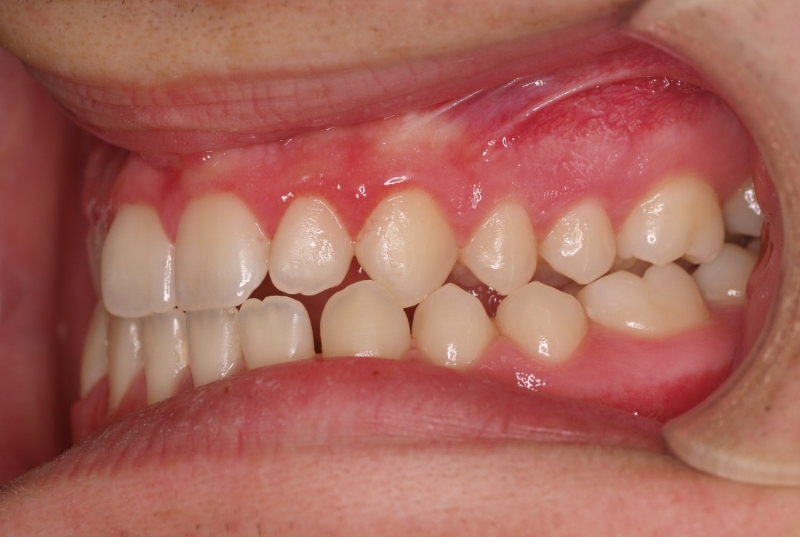

El paciente E.A. acude a nuestra consulta por diastema inferior y ausencia de contactos en los sectores laterales.

1) Arreglamos el problema funcional (lengua baja). Colaboramos con la logopeda Ana Muñoz.

2) Colocamos aparatología fija (brackets Damon) arriba y abajo.